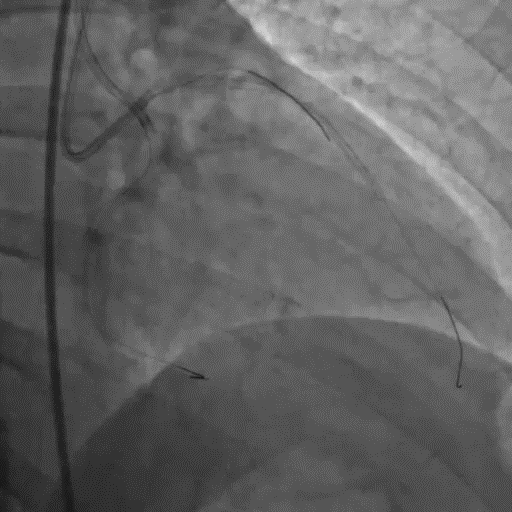

双侧造影明确LAD开口位置和临近血管关系。

Corsair135辅助下先后尝试使用P200/G3导丝未能突破近端纤维帽,最终CP12突破后进入血管结构内,同时进行多角度确认。

尝试调整导丝重回真腔未成功,直接使用XTA导丝knuckle。

跟进corsair并交换LP球囊后,先后尝试G3/CP12/8-20等导丝穿刺均失败。

直接尝试逆向,RCA中段3.0*10切割后,使用Finecross150+SUOH03通过心外膜逆向进入LAD,FC轻松跟进。

使用P200导丝攻击远端纤维帽前进困难,更换G3进入LAD近段内膜下,直接使用Telescope™导引延长导管辅助下AGT技术,r-CART后G3顺利进入Telescope™导引延长导管。

直接使用G3导丝rendezvous,球囊扩张后行IVUS检查确定血管直径及支架落脚点。